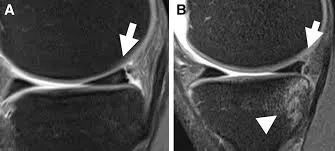

Hash等指出,Ramp损伤在MRI上的最突出 标志是在内侧半月板后角与后内侧关节囊之间插入了一个薄层的液体信号,观察内侧半月板后角与滑膜分离征象。

病例图片(均来自网络):